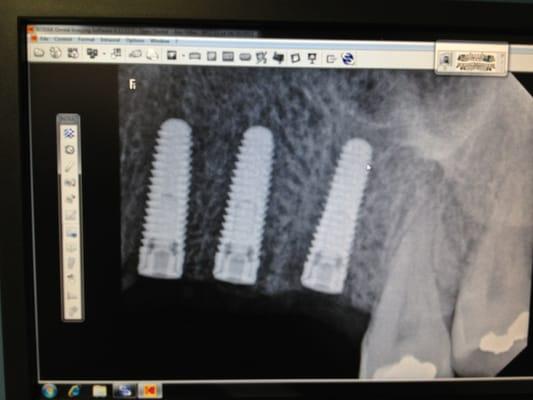

Photos